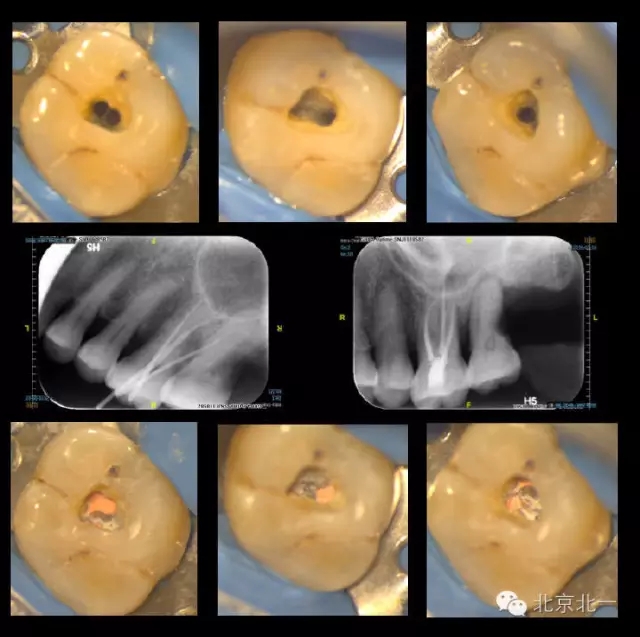

再看我們的現(xiàn)實,在我們的日常工作中,也一直期望能對微創(chuàng)開髓多有嘗試,可惜的是由于我國患者的口腔保健意識還有待提高,很多來牙髓病??凭驮\的患者牙體本身由于病變已沒有微創(chuàng)的可能。前段時間終于等到了這么一例牙周牙髓聯(lián)合病變,患者有著強烈的保留牙齒的愿望,但在牙周治療中并發(fā)了牙髓炎的癥狀,因此轉(zhuǎn)診至牙體牙髓專科需要進行根管治療。

對于這個冠部牙體組織完好的病例,我們也確實想給她盡量保留健康組織,于是就開始了對這個病例的微創(chuàng)治療。

根充完成后,用樹脂對牙齒進行了充填(由于是急診患者,很遺憾忘了拍攝術(shù)前照)。